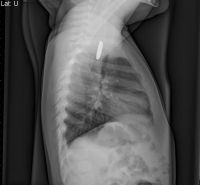

“I have seen many otherwise healthy children suffer serious injury from button batteries,” said Dr. Jatana, also an assistant professor of Otolaryngology-Head and Neck Surgery at The Ohio State University College of Medicine. “While educating parents about the dangers of these batteries is important, it is equally important for physicians to be aware of the increasing frequency of button battery ingestions when evaluating children in the primary care or emergency room setting. An x-ray can be done to confirm the diagnosis.” If a child is suspected of swallowing or pushing a button battery into their nasal cavity or ear canal, the child needs to be taken to an emergency room immediately. The diagnosis can be confirmed by a two view x-ray, which from a distance, may be mistaken for a commonly ingested foreign body in children – a coin. The key to differentiating a button battery from a coin is to magnify or zoom into the image to look for the double ring or halo seen around the button battery. In addition, on the side view x-ray, one can often see a small step-off or notch with most batteries. “Identifying a metallic foreign body as a button battery is critical as the battery creates an electrical current around the outside of the battery generating hydroxide, an alkaline chemical, causing the rapid tissue injury,” said Dr. Jatana.

The key to differentiating a button battery from a coin is to magnify or zoom into the image looking for a double ring or halo. This x-ray shows a small ridge on the object that this toddler has swallowed – a button battery.

While coins and button batteries look very similar and are of equal size, button batteries can cause severe damage if not removed quickly after it is ingested.